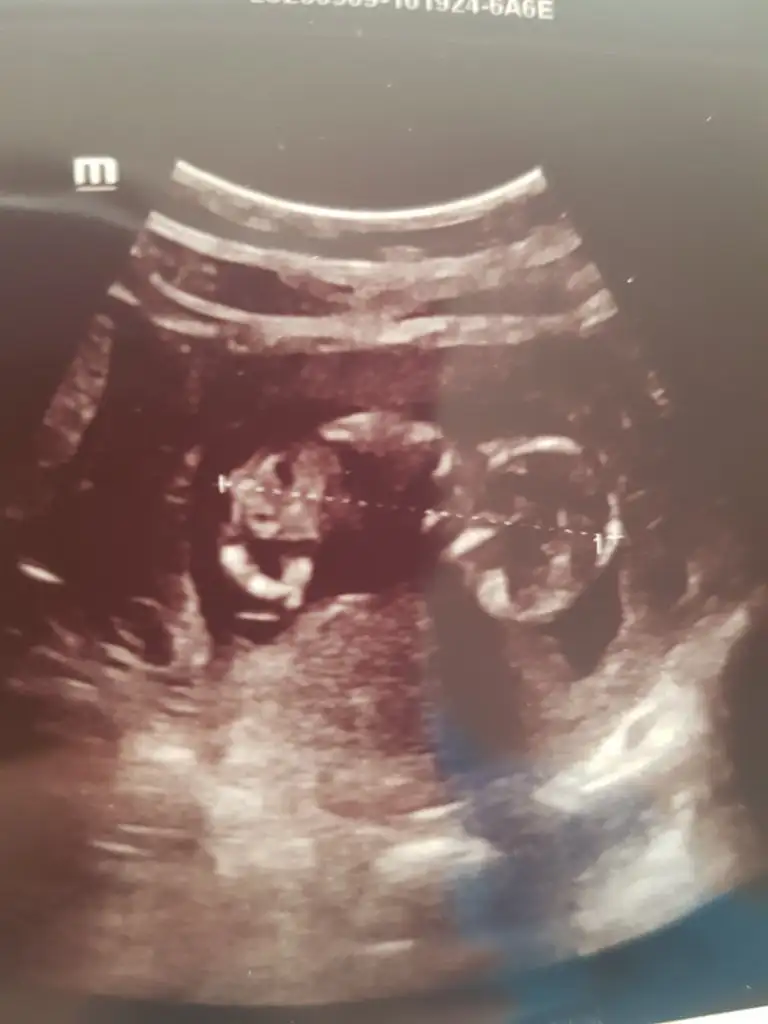

Doktor erkek dedi ama 12.hafta olunca ben emin olamadım. Pipi fotosu da vermiş, ona da bakınca çok emin olamıyorum. Belli bir aya dek benzer gittiği için genital organlar, belki yanılmıştır diyorum..kız istediğim için..umarım bir ay sonra, yanılmışım, kızmış der doktor..